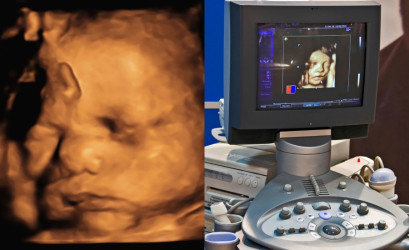

Depositphotos

Priebeh NIPT testu

NIPT test prebieha úplne neinvazívne – stačí štandardný odber krvi matky z žily, podobne ako pri bežných laboratórnych testoch. V tejto vzorke sa následne v laboratóriu analyzujú fragmenty DNA plodu, ktoré prirodzene kolujú v krvnom obehu tehotnej ženy.

Zdroj úvodnej fotky: Depositphotos